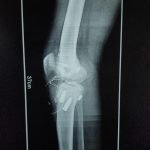

Orthopaedic Surgeon | Arthroscopy & Joint Replacement Specialist

Dr. Aditya Tripathi is a dedicated and skilled Orthopaedic Surgeon specializing in sports injuries, arthroscopy, and joint care. Known for his clinical precision, ethical practice, and patient-first approach, he focuses on helping patients regain mobility, strength, and confidence through evidence-based orthopaedic treatment. His academic background and hands-on clinical training reflect a strong foundation and a commitment to excellence in orthopaedic care.

Dr. Aditya Tripathi is widely appreciated by patients for his clear communication, honest medical guidance, and personalized treatment approach. His expertise in managing ACL tears, ligament injuries, shoulder conditions, and sports-related injuries makes him a trusted choice for comprehensive orthopaedic and sports injury care. Patients value his attention to detail, compassionate care, and focus on long-term recovery—establishing him as a reliable and respected orthopaedic specialist.

- ACL Reconstruction

- PCL Reconstruction

- Fracture Treatment